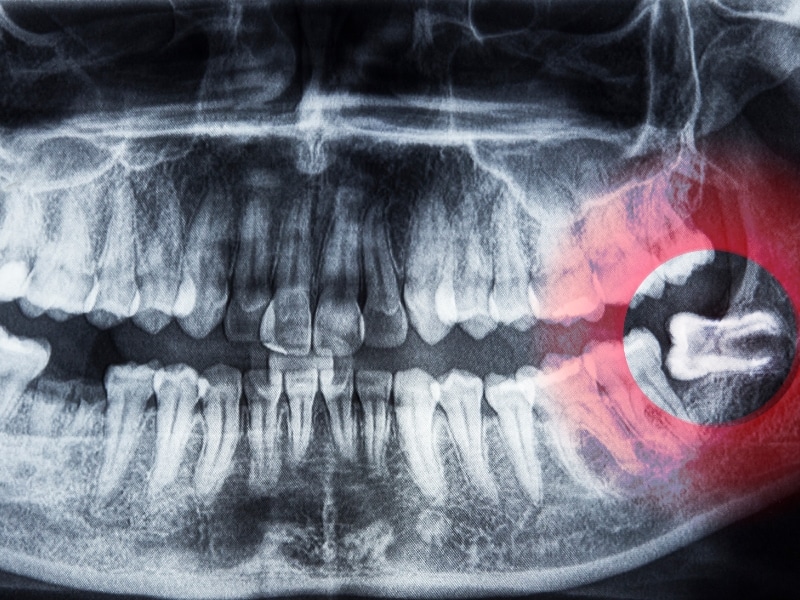

- Consultation and imaging: Usually includes a panoramic X-ray so your dentist can plan the best approach.

| X-rays | Show tooth position and root structure |